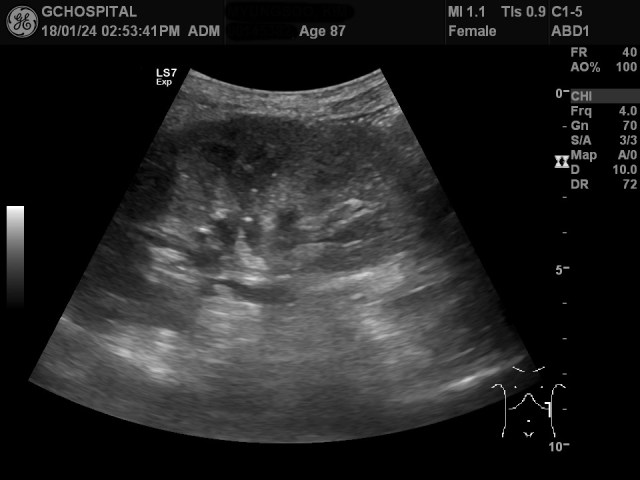

이러한 작은 단순낭종이 아래쪽에도 더 있을까 확인해보려 했지만, 좌측 신장이 흉곽 안에 들어있고, 환자분이 고령에 굉장히 깡마른 상태여서 시야가 잘 확보되지 않았습니다. 위 영상에서도 앞서와 비슷한 1센티미터 이하의 단순낭종이 신장 피막 바깥쪽으로 튀어나온 것이 보이지만, 이 외에도 좀 애매하게 안보이는 낭종들이 보여서 선형탐촉자를 갈비뼈 사이로 위치해서 더 확인해봤습니다.

방금 전에 신장 피막 바깥쪽으로 보였던 단순낭종이 훨씬 더 뚜렷하게 보입니다.